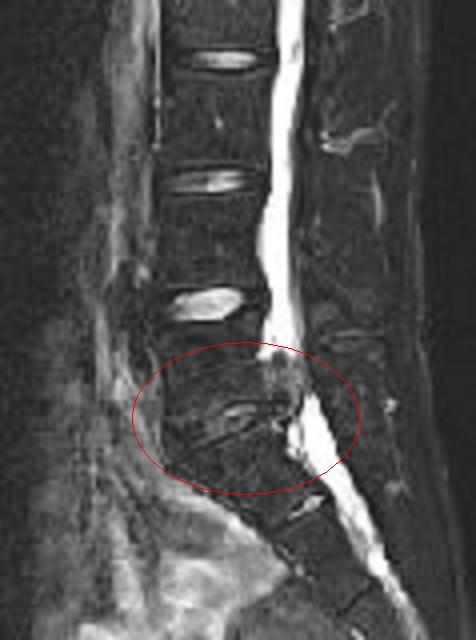

MRI로 나타난 척추 추간판 탈출증

'''빨간 원 안은 '압박된 신경근' 및 '수분 함량이 부족하고 염증을 일으켜 위로 크게 돌출된 추간판'''']]

'''추간판 탈출증 MRI 이미지 II-②'''

'''위 이미지의 고농도 버전'''